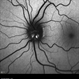

- Bilateral benign yellow dot maculopathy

- yellow dots, Autoflourescence

- A 37-year-old female patient presented for a routine eye examination. Her best-corrected visual acuity was 6/6 in both eyes. Fundus examination revealed multiple small yellow dots over the macula in both eyes. FAF imaging demonstrated characteristic hyperautofluorescence corresponding to these dots.